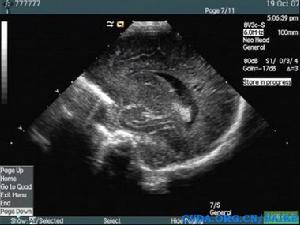

超聲診斷

腦白質軟化早期超聲可見腦室周邊白質回聲增強,邊界不清,沒有占位效應,如果沒有這方面的意識,此時容易漏診,因此在顱腦超聲檢查時,能夠顯示各個腦室的切面均需觀察其附近腦白質回聲是否均質,有無回聲增強,隨著時間推移,其內可見液性囊區,比較容易被超聲發現!新生兒缺血缺氧性腦病、顱腦損傷為常見病因。

一般這種患兒多在新生兒期檢出,有顱內感染、宮內感染或者產傷的病史,顱腦超聲檢查時需注意腦白質回聲是否均質,早期病變與周圍正常組織對比度不是很明顯,易漏診!